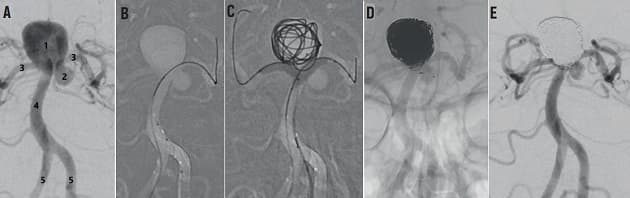

© Digital subtraktionsangiografi, der illustrerer endovaskulær behanding af subaraknoidalblødning.

Subaraknoidalblødning er en alvorlig tilstand med betydelig morbiditet og mortalitet. Diagnosen kan være svær ved atypiske symptomer og forløbet kan blive kompliceret af reblødning og hydrocephalus, og såkaldt delayed cerebral ischaemia, hvorfor korrekt diagnostik er vigtig med henblik på hurtig overflyttelse til et neurocenter med mulighed for neuroanæstesiologisk, neurokirurgisk og interventionsradiologisk behandling.